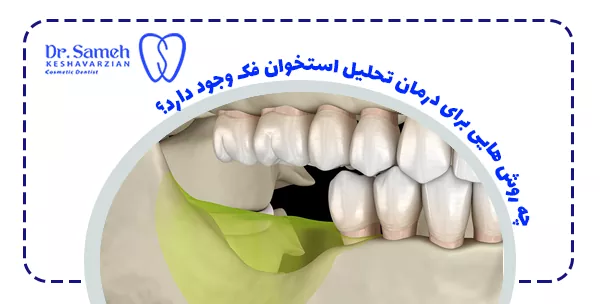

چه روش هایی برای درمان تحلیل استخوان فک وجود دارد؟

پیشرفت های علم دندانپزشکی روش های موثری برای درمان این مشکل فراهم کرده است:

- پیوند استخوان: استفاده از بافت استخوانی خود فرد یا مواد مصنوعی برای بازسازی ناحیه تحلیل رفته

- لیفت سینوس: افزایش ارتفاع استخوان در ناحیه فک بالا با جراحی سینوس

- روش های بازسازی هدایت شده با غشاهای مخصوص

- استفاده از فاکتورهای رشد و سلول های بنیادی در درمان های نوین